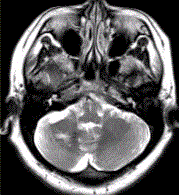

问题 患者女,41岁。头痛半年,加重10d。头部MRI显示如下图。 关于发育性静脉畸形的描述正确的是

选项 A.MR增强检查显示“海蛇头”样表现 B.常发生于侧脑室额角白质或Ⅳ脑室周围白质 C.扩张的髓静脉呈伞样汇集,经粗大的静脉引流入静脉窦或深部室管膜静脉 D.病变较小,T1WI可正常,T2WI可见血管流空 E.影像学首选MRT1C+MRV F.T2*WI可显示出血及伴有其他血管畸形 G.15%~20%伴有海绵状血管瘤